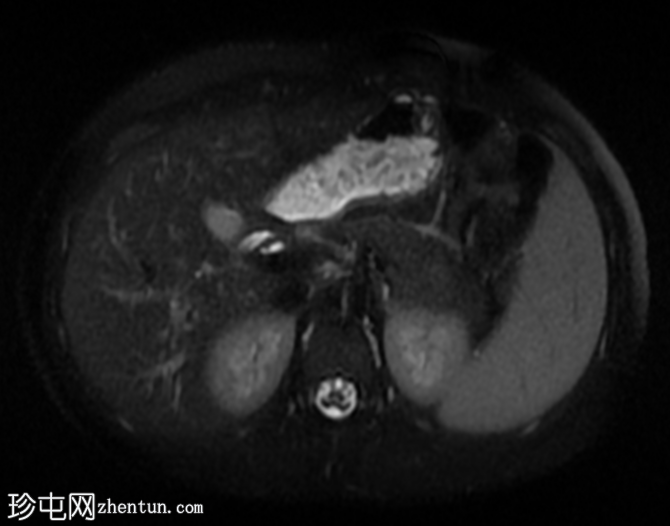

轴位

T2加权像

子宫前倾位,分区解剖结构正常。矢状位序列可见子宫前壁肌层局灶性边界不清的低信号病灶,但在后续序列中未见明显,符合短暂的生理性子宫肌层收缩表现。

双侧卵巢大小及卵泡活动均正常。未见囊性或实性肿块。

腹部MRI检查结果正常。

该病例的盆腔器官MRI表现与患者年龄(14岁)相符,子宫位置正常,分区解剖结构正常,双侧卵巢大小及卵泡活动均正常,未见囊性或实性肿块。

此外,MRI还意外发现子宫肌层局灶性病变,T2信号低,易被误诊为子宫肌瘤。然而,该病变在后续序列中消失,符合短暂的生理性子宫肌层收缩所致。